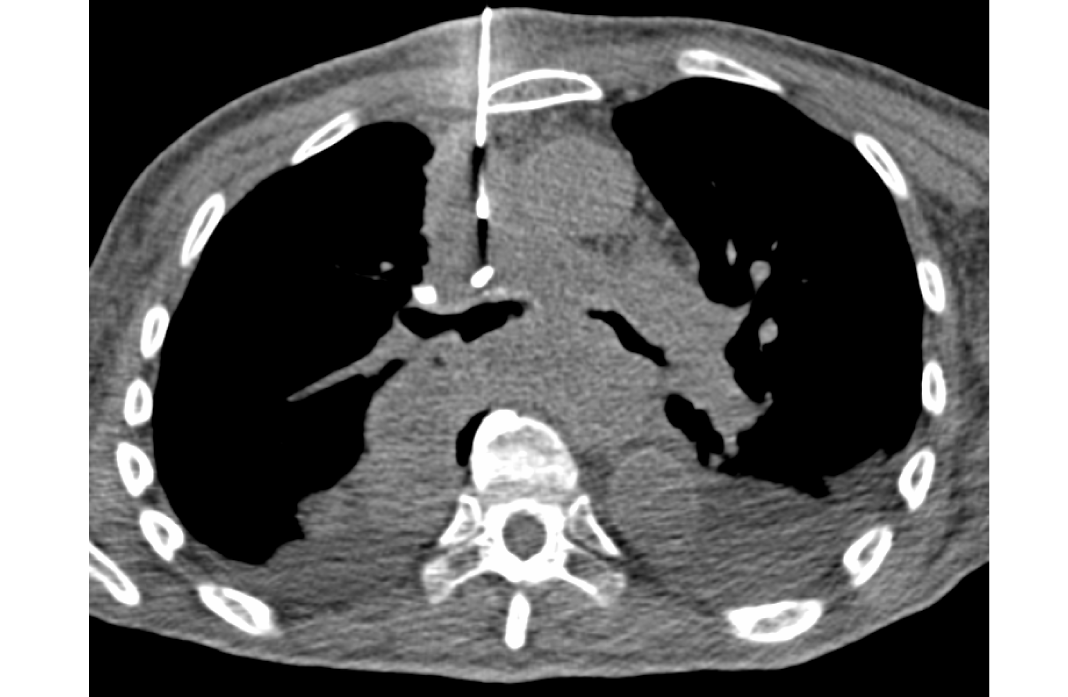

Síndrome de vena cava superior